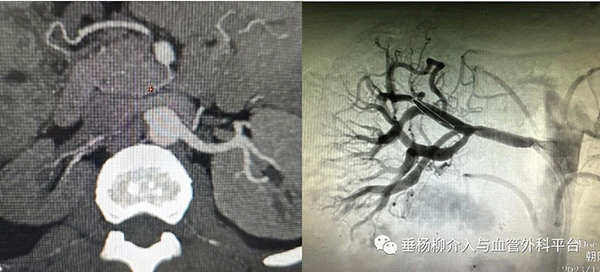

肾血管相关检查:包括超声波、CT血管成像或核磁共振等影像学检查,以确认肾动脉狭窄的情况。

介入治疗:适用于病变部位可达的情况。常用的介入治疗方法是经皮肾血管成形术,可以消除或缓解肾动脉狭窄,从而减轻高血压程度。